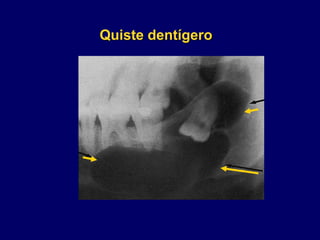

Quiste dentígero

• 27.